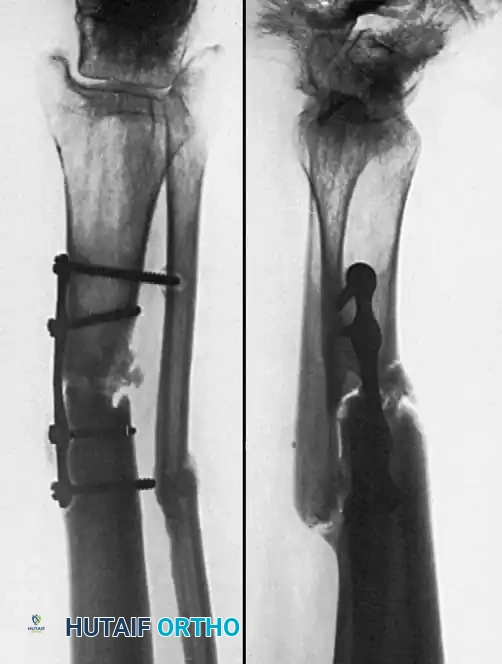

Associated Surgical & Radiographic Imaging